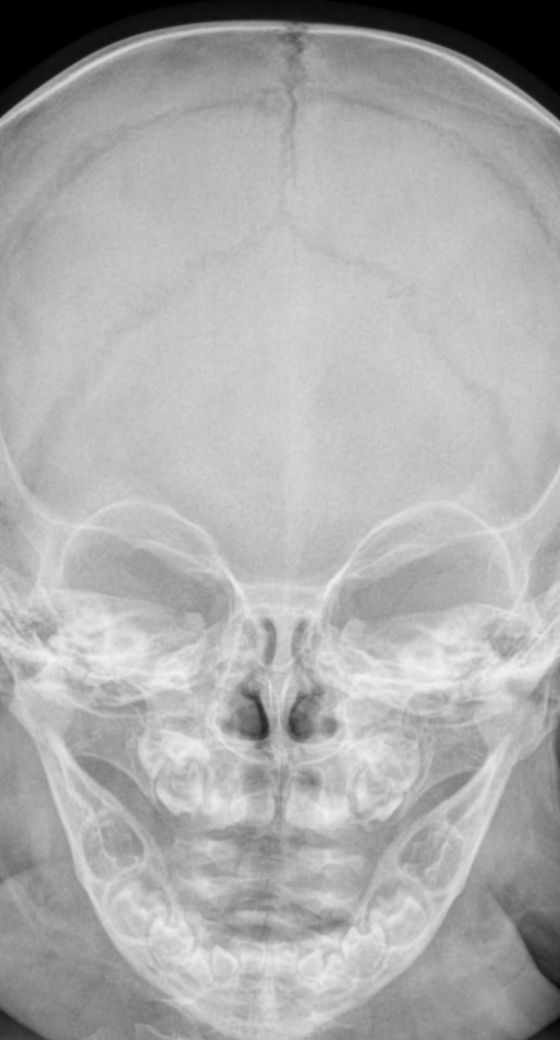

엑스레이 연한 흰 선 의미는 무엇인가요?

6개월 아기입니다.

엑스레이 전두 봉합선이 비교적 연해 보이는데 맞나요?

연한 흰선이라면 붙은지 오래된건가요?

아니면 비교적 최근에 붙은 것으로 해석할 수 있나요?

• 어떠한 것을 이야기 하시는 것인지 모르겠습니다. 올리신 두개골 엑스레이 사진에는 딱히 이상 소견이 보이거나 하지는 않긴 합니다.